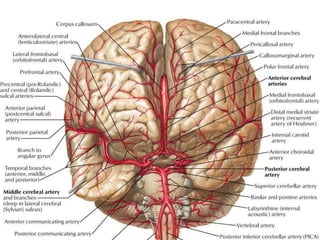

Giải phẫu

động mạch não

• Động mạch cảnh trong

• Động mạch đốt sống

Đa giác Willis

Vùng tưới máu

ACA MCA PCA

Nhìn trên Nhìn dưới

Tắc ACA

Tắc MCA

Tắc PCA

Giải phẫu động mạchnão • Động mạch cảnh trong • Động mạch đốt sống